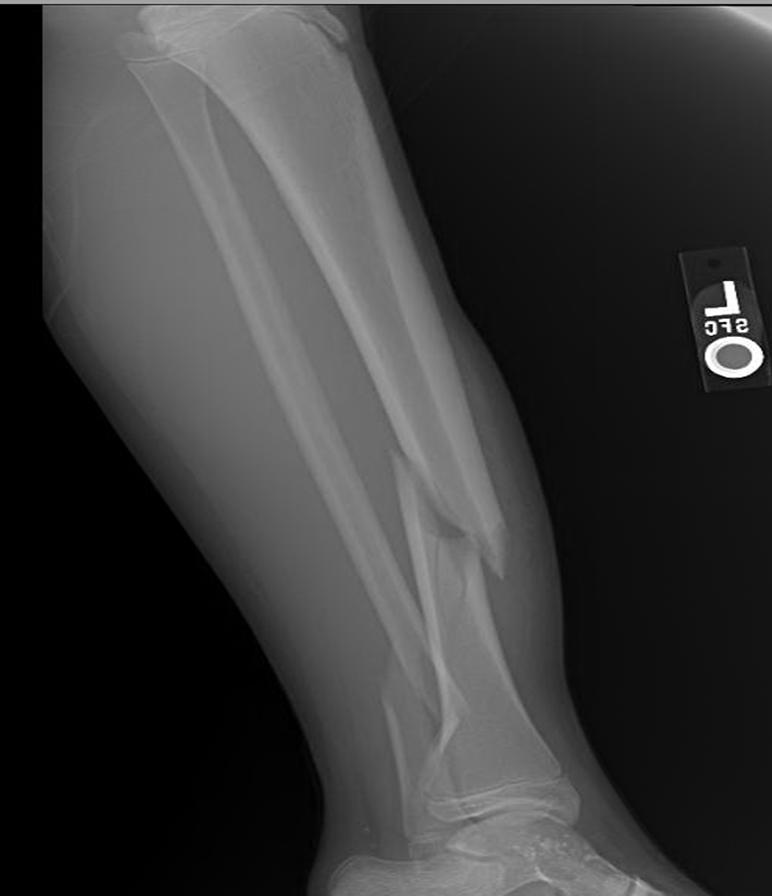

Tibial Shaft Fractures Trauma Orthobullets

Sequence showing an fracture of tibia showing left to Broken Tibia Cast A study of cadavera with use of a magnetic motion sensor. Full recovery can take at least a year and sometimes two. Learn about tibia shaft fractures, the most commonly fractured long bone in the body. Analysis of external fracture immobilization in anatomic specimens in casts and braces. Learn about the causes, symptoms and treatments of broken shinbone or calf. Broken Tibia Cast.

Tibia and fibula, shaft simple fracture, oblique Musculoskeletal Key Broken Tibia Cast A tibia fracture is a break in the shinbone, which is the most common long bone in the body to fracture. A study of cadavera with use of a magnetic motion sensor. Analysis of external fracture immobilization in anatomic specimens in casts and braces. Learn about the causes, symptoms, diagnosis, and treatment options for a. Control of motion of tibial. Broken Tibia Cast.